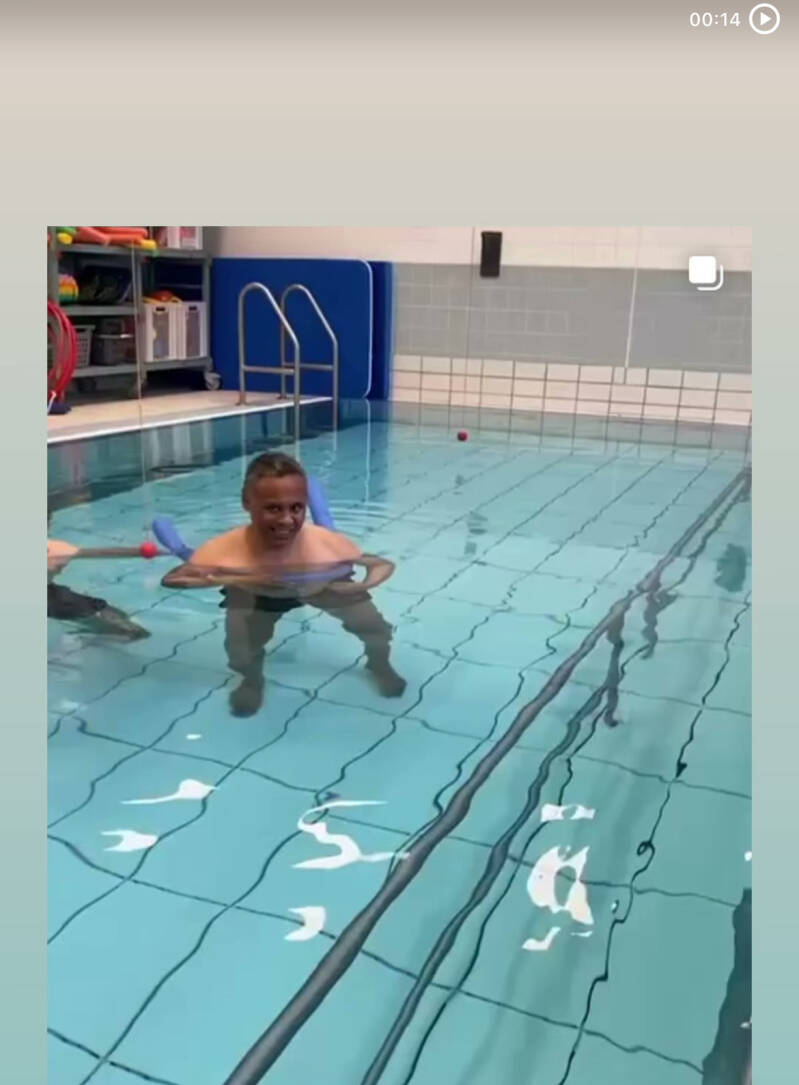

eerstekeerzwemles

Na mijn herseninfarct heb ik staand badminton en het zwemmen herontdekt. Ook fiets ik weer regelmatig. Deze sporten geven mij energie en helpen mij om fit te blijven. Het is geweldig om te ervaren dat ik nog steeds actief kan zijn en plezier kan hebben in sport, ondanks mijn beperkingen.